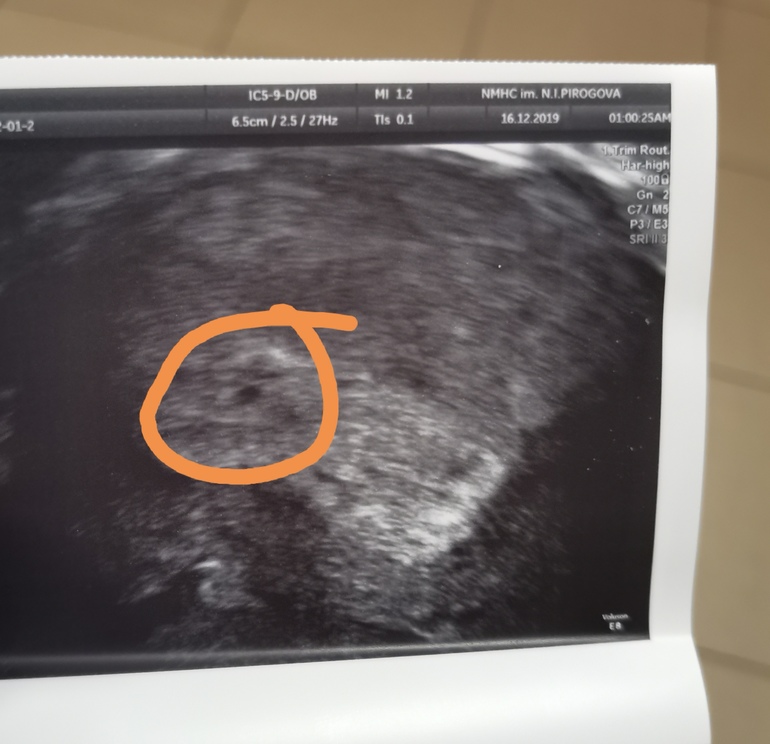

Получила на руки первую картинку узи.

Ре сказала, что точка, которую я обвела - это будущий малыш.

И вот моя мнительность не дает мне покоя, поскольку я нашла еще целых три точки...

Узисту надо показать. Мне кажется, что пя не черная точка внизу, а такая обведенная белым чуть повыше. Вот она одна такая, и в оболочке. Но я не специалист. В любом случае поздравляю вас.